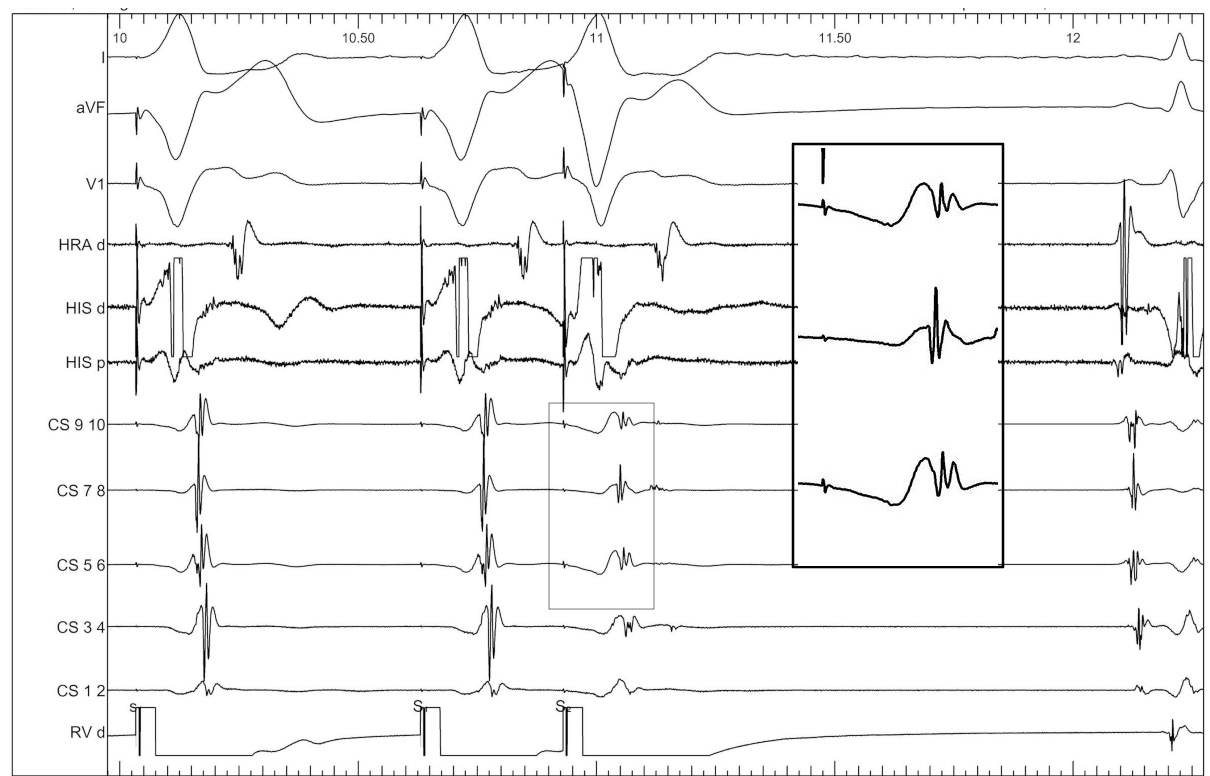

Atrial S1S2 - 600/290 ms

05_ra_600_290.jpg

Parahisian pacing

06_parahisian.jpg

AF induced

07_af.jpg